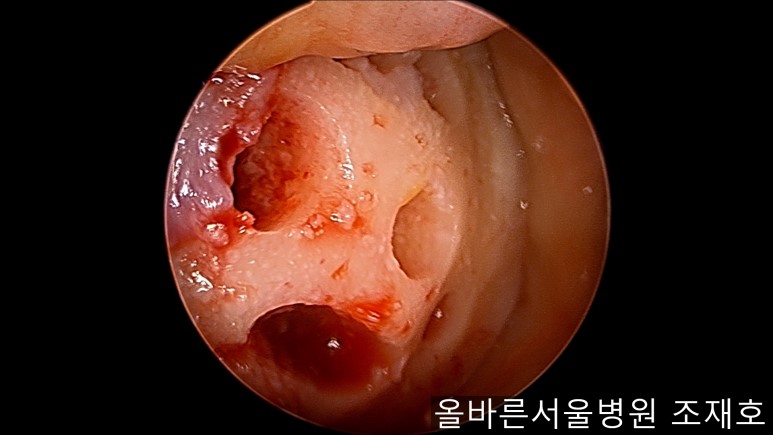

通过关节镜图像可看到:由于内侧股骨髁软骨损伤骨头已经显露出来。

胫骨上端的软骨损伤严重,也露出了骨头。

正是缺失软骨的部位碰到一起,引发剧烈疼痛,腿部逐渐变形。

与内侧对照,外侧的软骨及软骨板无损伤。